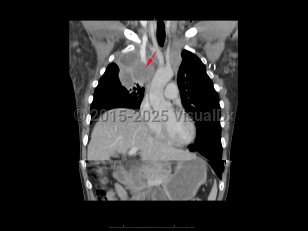

Anasarca, 50-59 year old Female

Pericardial effusionPericardial effusion